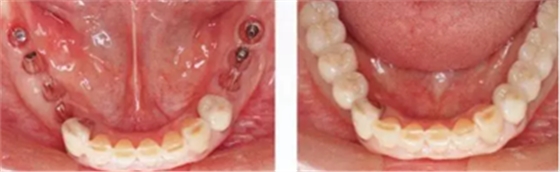

▲圖10-3,4

圖10-3 第二次手術(shù)前的(牙合)面照。

圖10-4 為了在頰側(cè)、舌側(cè)進行FGG,在上頜腭側(cè)采集大塊移植片

▲圖10-5,6

圖10-5 第二次手術(shù)后的舌側(cè)面照。遠中側(cè)進行APF,近中側(cè)進行FGG。

圖10-6 頰側(cè)也進行FGG,縫合后確認移植片不會移動。

▲圖10-7,8

圖10-7 術(shù)前。

圖10-8 術(shù)后。種植體周圍獲得了充足的角化齦。